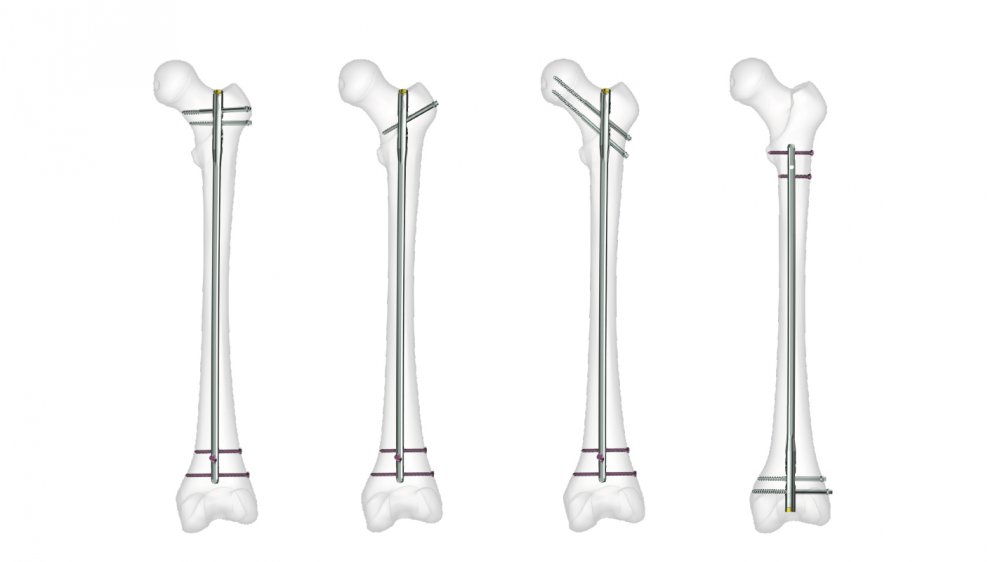

Hip fracture surgery may seem challenging, but it is considered a suitable treatment option for fractures in the hip area. The patient should see a doctor immediately to determine the appropriate treatment method and realign the fractured bones to their natural position. This can be done through either an incision in the hip area or by inserting screws or metal plates. Patients can typically leave the hospital after about two weeks, and complete recovery may take from 3 to 6 months.

Hip fracture surgery can be scary for many people, and some may wonder if the bone returns to its normal state after the fracture. In reality, treating a hip fracture requires a surgical procedure, and the doctor may be able to realign the fractured bones after the break. This is done through a surgical procedure that involves proper fracture repair and stability of the bones using special plates. Therefore, hip fracture surgery should be performed under the supervision of a qualified surgeon after a comprehensive assessment of the case.